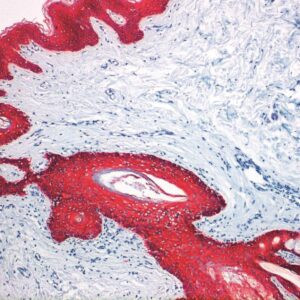

Anti-YAP

YAP encodes a nuclear effector of the Hippo signaling pathway which plays a pivotal role in regulating tissue growth and organ size. Deregulation of the Hippo pathway causes tumor formation and malignancy and hence, YAP may function as a potential target for cancer treatment. YAP is expressed at high levels in the lung, placenta, prostate, testis and ovary.